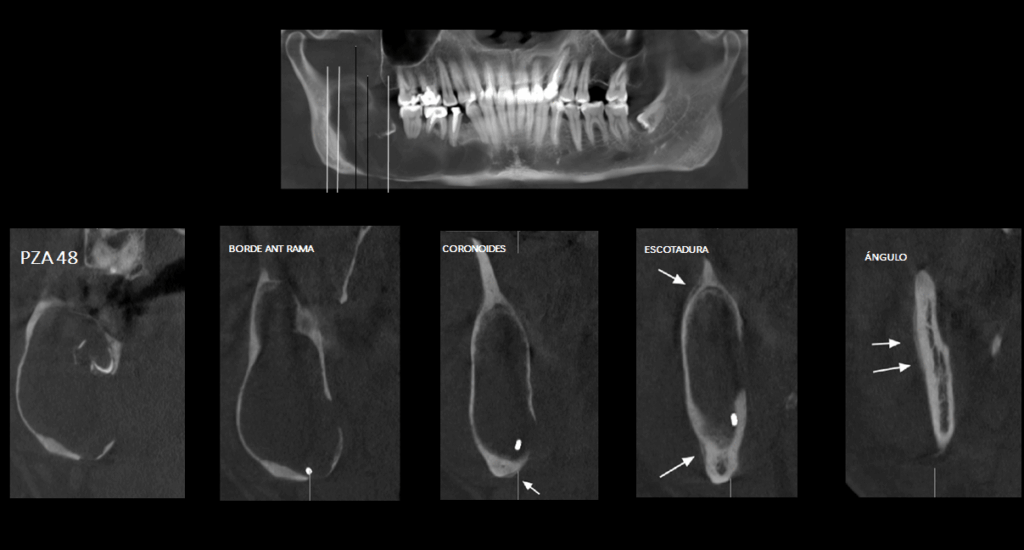

En la radiografía panorámica (Figura 1), se observa una lesión radiolúcida de limites definidos y bordes parcialmente corticalizados ubicado en cuerpo, ángulo y rama mandibular de lado derecho con una extensión desde pieza 44 hasta rama ascendente mandibular y desde la escotadura antegoneal hasta la basal mandibular, ocasionando expansión en el borde anterior de la rama y reabsorción externa en piezas 46 y 47. Además se observa una imagen radiopaca irregular en el interior de la lesión en zona de pieza 48.

Radiografia Panorámica

A la evaluación de la tomografía volumétrica (cone beam) bimaxilar en los cortes axiales (Figura 2), coronales, (Figura 3) y tangenciales (Figura 4) se observa imagen isodensa irregular, ubicado en cuerpo, ángulo y rama ascendente mandibular de lado derecho, que se extiende desde zona periapical mesial de pieza 44, hasta tercio medio de rama mandibular, y desde tercio superior (próximo a base de apófisis coronoides) hasta basal mandibular ocasionando expansión de tablas ósea, adelgazamiento de corticales y pérdida de continuidad de tabla vestibular en zona de pieza 45 y de tabla ósea lingual a en zona de pieza 46, 48 y rama mandibular. Además de producir el desplazamiento caudal y borramiento parcial de las corticales del canal mandibular; así mismo, se observó reacción periostal en tabla ósea vestibular (próxima a escotadura sigmoidea), ángulo mandibular y en basal mandibular de zona antegonial. Se pudo evidenciar tambien a la pieza 48 incluida y con reabsorción severa 48 dejando solo restos de esmalte.